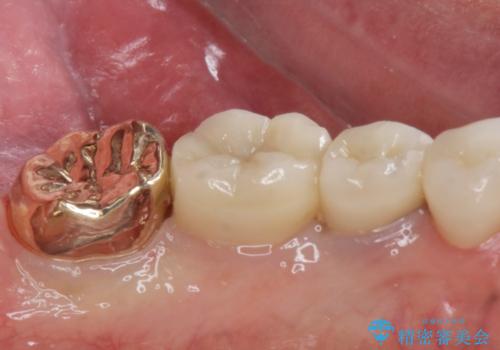

ゴールドクラウン

- 過去に治療したゴールドの詰め物が取れて来院。取れたのは2回目だそうです。レントゲンでは適合が良いので再装着可能だったが、

もう取れたくないとの事だったので被せ物のご案内をしました。ゴールドの被せ物の希望だったのでゴールドクラウンでの治療になりました。

- ゴールドクラウン・仮歯 13.2万円費用は治療当時の料金となります

適合の良いゴールドクラウンが入りました。

ゴールドは適合が良く、割れる心配もありません。

また、虫歯になるリスクも銀歯と比べて低くなります。